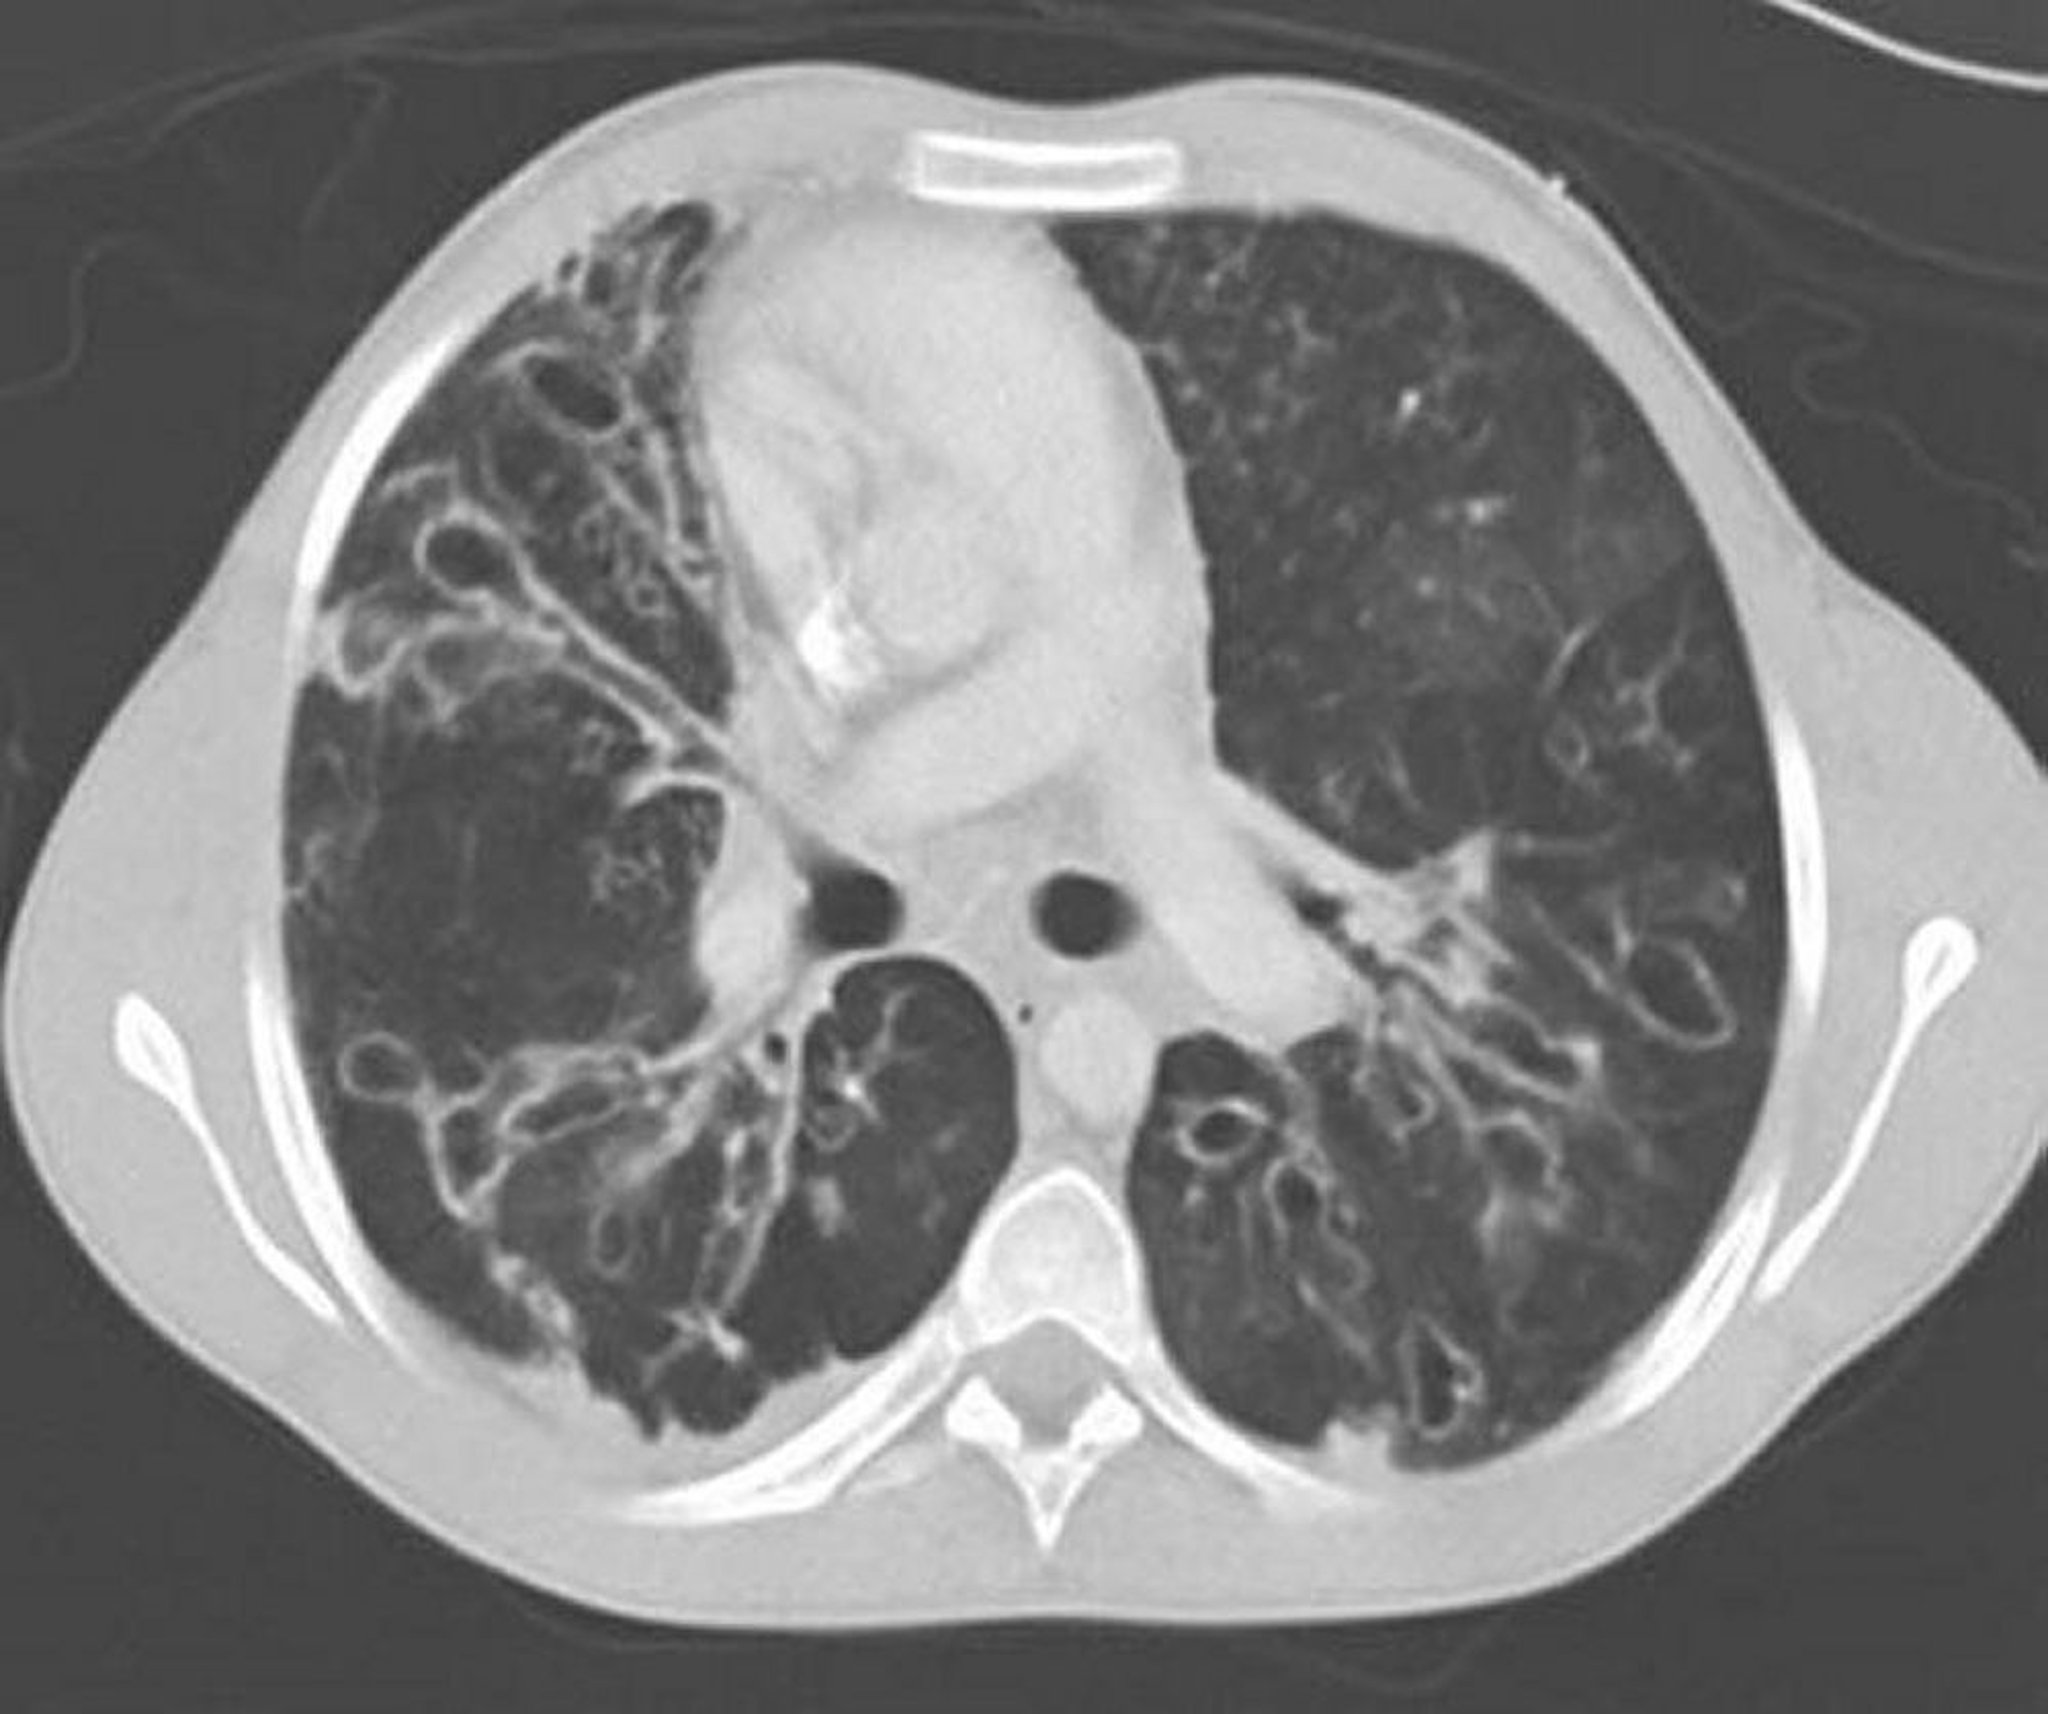

Aspergillosi broncopolmonare allergica (bronchiectasie)

Una TC torace con mezzo di contrasto mostra gravi bronchiectasie nei campi toracici medi con vie aeree dilatate ed ectasiche e alterazioni cistiche. L'ectasia delle vie aeree è caratterizzata da un rapporto tra le vie aeree e il vaso adiacente > 1.

By permission of the publisher. Da Coakley R, Boucher R, Fiel S, et al. In Bone's Atlas of Pulmonary and Critical Care Medicine. Edited by J Crapo. Philadelphia, Current Medicine, 2005.